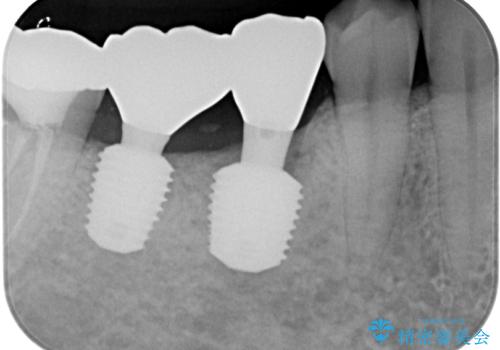

- むし歯を放置したことで、歯茎で膿が腫れ上がったしまったとのことで来院された患者様です。

ブリッジの支台歯が痛みを覚え、近医でブリッジを切断してもらって以降、そのままにしてしまったとのことでした。

問題が起きていた手前の歯から膿が出てきたことを自覚して当院を来院されましたが、既に歯根破折をしており、抜歯が必要な状態でした。

咬合力が非常に強い患者様であり、2歯欠損のブリッジ(しかも大臼歯は失活歯)は歯根破折のリスクが高すぎると判断し、抜歯部および欠損部に対して、インプラントによる補綴治療を行うこととしました。